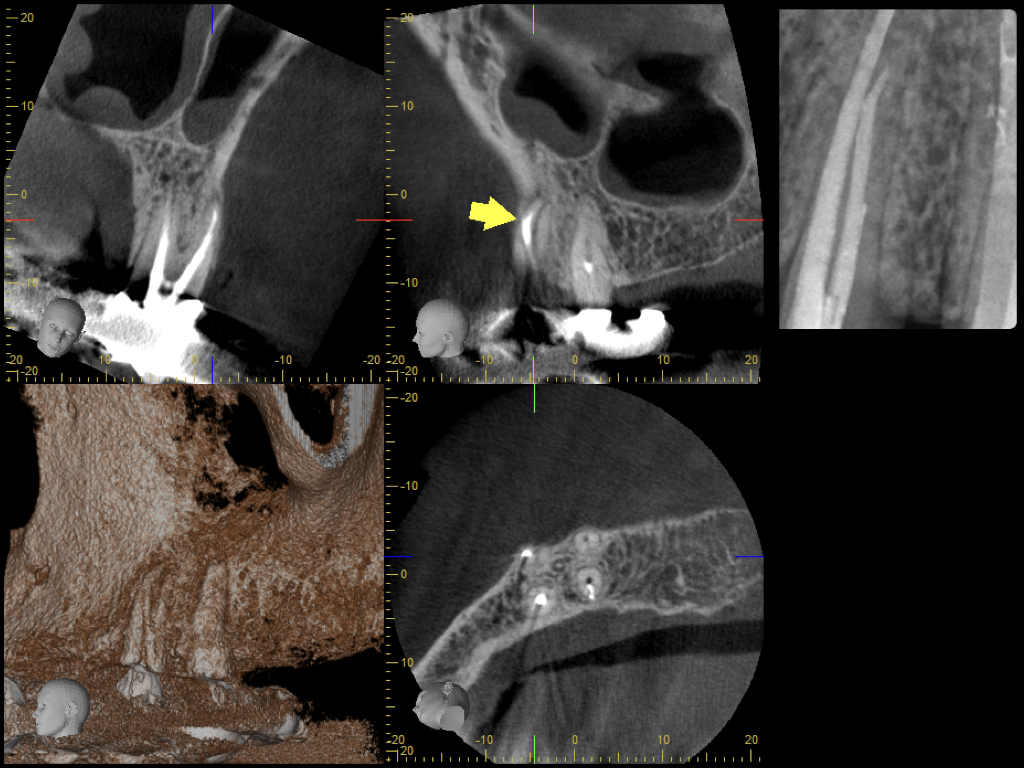

Es ist zu sehen … (2)